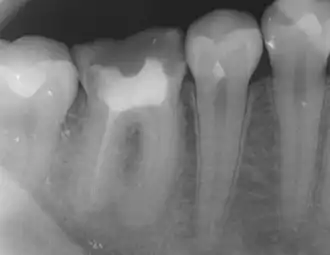

The body's response to microbial invasion

.jpg)